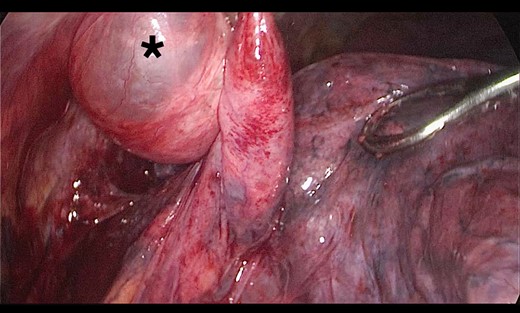

A 73-year-old male patient with a clinical history of COPD, lung emphysema and a 30-year smoking history was admitted to the ED due to a 24-h clinical picture of dyspnea immediately following a sudden bout of dry coughing. Physical examination showed a dyspneic patient, tachypnea of 25 rpm, heart rate of 85 bpm and blood Pressure of 135/75 mmHg along with central cyanosis. Chest exam showed a hyper-resonant right hemithorax along with reduced breath sounds. Initial chest X-ray revealed a large right-sided pneumothorax (Fig. 1). A right chest tube was placed in the ED. Emergency echocardiogram had no significant findings and spirometry showed suspected patterns of obstruction. Following patient stabilization, a high-resolution chest computed tomography (HRCT) was performed revealing extensive pan lobar emphysema throughout both lungs, para septal emphysema in both the anterior upper lobes and herniation of a left lung bullae through the anterior mediastinal pleura along with a right-sided pneumothorax with the chest tube in place with persistent air space (Fig. 2). The patient was taken to surgery where a right video-assisted thoracoscopic (VATS) approach showed severe lung emphysema and a contralateral herniated left lung bulla through the mediastinal pleura anterior to the pericardium (Fig. 3). Right pleurodesis was performed using Talc and a left posterior thoracoscopy showed a severe emphysematous left lung with a lingular herniated bulla to the right hemithorax through an anterior mediastinal pleural defect along with pleural adhesions (Figs 4 and 5). Thoracoscopic hernia reduction was performed along with bullectomy using 60 mm mechanical sutures (Fig. 6). Chest tubes were removed on POD 3 (right) and POD 4 (left). The patient had significant respiratory improvement and was discharged on POD 5.

Thoracoscopic view of transmediasinal herniation of pulmonary bulla to the right hemithorax (asterisk).